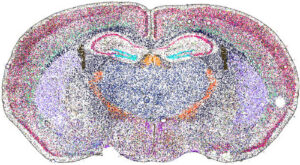

Spatial biology is a rapidly advancing discipline that examines biological molecules (such as DNA, RNA, and proteins) within their native locations in tissues. This approach offers critical insight into how cancer and immune cells interact within the tumor microenvironment.

Beginning in the 20th century, techniques such as immunohistochemistry and in situ hybridization allowed researchers to localize proteins and nucleic acid sequences directly in tissue samples. However, these analyses were typically limited to a single marker at a time. More recently, advances in high-throughput sequencing and mass spectrometry enable the simultaneous analysis of hundreds, or even thousands, of molecules while preserving spatial context. To explore the future of spatial biology, we spoke with four companies pioneering these technologies.

The transcriptome is the complete collection of RNA produced in a cell or tissue at a given time. It reflects active gene expression, which varies with disease state and environmental conditions. Understanding the transcriptome is therefore crucial for studying cancer biology and treatment response.

Pratheesh Sathyan, PhD, head of AMR oncology at Illumina, says that the company plans to roll out a new spatial transcriptomics platform for commercial release in 2026. He describes several advantages of spatial transcriptomics.

“Immune cells are an important part of our defense against cancer. And spatial approaches help to understand how immune cells interact with the tumor,” he says. “With spatial transcriptomics, you are maintaining the true habitat of the tissue, and that helps us with better diagnostics and better precision therapy.”

Since then, a great deal of progress has been made in the field. Segale notes that Illumina’s platform will enable sampling of more than seven square centimeters of tissue. “This allows you to look at large bits of tumor microenvironments. More than other products available today,” he says.

Another key feature of the upcoming product is whole transcriptome coverage. “Many spatial transcriptomics platforms look at panels of typically 5,000 unique transcripts,” notes Segale. “In contrast, we are seeing 30,000 to 40,000 unique RNA transcripts per sample. It is completely unbiased and hypothesis-free. There is a real richness of information that we are seeing.” Finally, the platform will enable 1-micron spatial resolution, allowing researchers to see key surface features on the cellular level.

“The information from our new platform will allow us to differentiate different cell types from one another and even identify new markers and new subtypes,” says Segale. “This is important because much of the cellular structure of the human body still has not been mapped, including organs and various tissues.”

Easterling recounts a collaboration with Stanford University and the Medical University of South Carolina to spatially localize glycans in different tissues. This information was then combined with spatial transcriptomics and proteomics layers to analyze gliomas, a lethal cancer with very limited treatment options. Ultimately, the glycomics information emerged as the strongest classifier of tumor grade across all three omics layers.